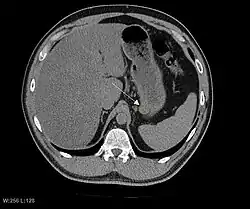

Радиологические исследования

Радиологические исследования используются для уточнения локализации новообразования, выявления признаков инвазии и метастазирования. Проявления ГИСО варьируют в зависимости от размера опухоли и поражённого органа. Диаметр опухоли может составлять от нескольких миллиметров до более 30 см. Крупные опухоли обычно вызывают клинические проявления, бессимптомные опухоли обычно небольших размеров и имеют лучший прогноз.[3][16] Большие опухоли чаще ведут себя более злокачественно, однако и небольшие ГИСО могут иметь агрессивное течение.[17]

Небольшие ГИСО

Так как ГИСО происходят из мышечного слоя (который располагается глубже слизистого и подслизистого слоёв), небольшие ГИСО чаще визуализируются как подслизистое или внутристеночное объёмное образование. При исследовании желудочно-кишечного тракта с барием обычно выявляются ровные контуры образования, формирующие прямой или тупой угол со стенкой, что наблюдается и при любых других интрамуральных процессах. Поверхность слизистой интактна, за исключением случаев изъязвления, которые присутствуют при 50 % ГИСО. При КТ с контрастным усилением, небольшие ГИСО обычно визуализируются как интрамуральные образования с ровными, чёткими контурами и гомогенным контрастированием.

Крупные ГИСО

По мере роста опухоли, она может проецироваться снаружи от органа (экзофитный рост) и/или в просвете органа (интралюминальный рост); чаще всего ГИСО растут экзофитно, таким образом большая часть опухоли располагается в проекции брюшной полости. Если увеличение объёма опухоли опережает рост её кровоснабжения, опухоль может некротизироваться в толще, с формированием центральной зоны жидкостной плотности и кавитацией, что может приводить к изъязвлению и формированию соустья с полостью органа. В этом случае исследование с бариевой взвесью может демонстрировать газ, уровни газ/жидкость или депонирование контрастного препарата в этих областях.[17][18] При КТ с контрастным усилением крупные ГИСО выглядят негомогенно, в связи с неоднородностью структуры опухоли, обусловленной участками некроза, кровоизлияниями и полостями, что радиологически проявляется контрастированием опухоли преимущественно по периферии.[16]

Злокачественность может проявляться локальной инвазией и метастазами, обычно в печень, сальник и брюшину. Однако встречаются случаи метастазирования в кости, плевру, лёгкие и забрюшинное пространство. По сравнению с аденокарциномой желудка или лимфомой желудка/тонкой кишки, злокачественная лимфаденопатия при ГИСО не типична (<10 %).[16] При отсутствии метастазов радиологическими признаками злокачественности являются большие размеры опухоли (>5 cm), гетерогенное контрастирование после введения контрастного препарата и наличие изъязвлений.[3][16][22] Также явно злокачественное поведение (без учёта опухолей со злокачественным потенциалом) реже наблюдается при ГИСО желудка, с отношением доброкачественных опухолей к явно злокачественным 3-5:1.[3] Даже в случае наличия радиологических признаков злокачественности, следует учитывать, что они могут быть обусловлены другой опухолью; окончательный диагноз должен быть установлен иммуногистохимическим методом.

Рентгенографические исследования с барием и компьютерная томография обычно применяются для обследования пациентов с абдоминальными жалобами. Исследования с барием выявляют патологические изменения в 80 % случаев ГИСО.[17] Однако некоторые ГИСО могут располагаться полностью вне просвета органа, что делает невозможным их выявление при исследовании с барием. Даже в случае выявления патологических изменений при рентгенографии с барием, необходимо последующее дообследование методами МРТ или КТ. КТ-исследование проводится с пероральным и внутривенным контрастным усилением, и позволяет визуализировать ГИСО в 87 % случаев[17] Мягкие ткани наиболее контрастны при МРТ, что помогает в выявлении интрамуральных образований. Для оценки васкуляризации опухоли необходимо внутривенное введение контрастного препарата.

Методами выбора в диагностике ГИСО являются КТ и МРТ,[23]:20–21 и, в некоторых случаях, эндоскопическое УЗИ. Томографические методы позволяют уточнить органную принадлежность опухоли (что может быть затруднительно при её больших размерах), визуализировать инвазию в соседние органы, асцит и метастазы.